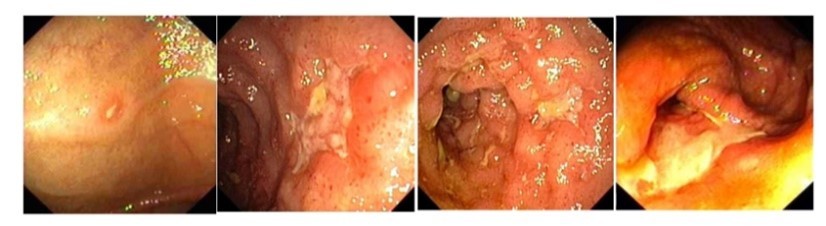

Vad visar bilden och vad kan sjukdomen ge upphov med tiden?

Crohns sjukdom, geografi och utbredning?

Vilken sjukdom och vad visar bilden?

Vilken sjukdom och vad är speciellt med sjukdomen i förhållande till bilden?

Ulcerös kolit